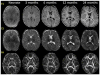

Diffusion tensor imaging (DTI) is an MRI technique that can measure the macroscopic structural organization in brain tissues. DTI has been shown to provide information complementary to relaxation-based MRI about the changes in the brain's microstructure. In the pediatric population, DTI enables quantitative observation of the maturation process of white matter structures. Its ability to delineate various brain structures during developmental stages makes it an effective tool with which to characterize both the normal and abnormal anatomy of the developing brain. This review will highlight the advantages, as well as the common technical pitfalls of pediatric DTI. In addition, image quantification strategies for various DTI-derived parameters and the normal brain developmental changes associated with these parameters are discussed.